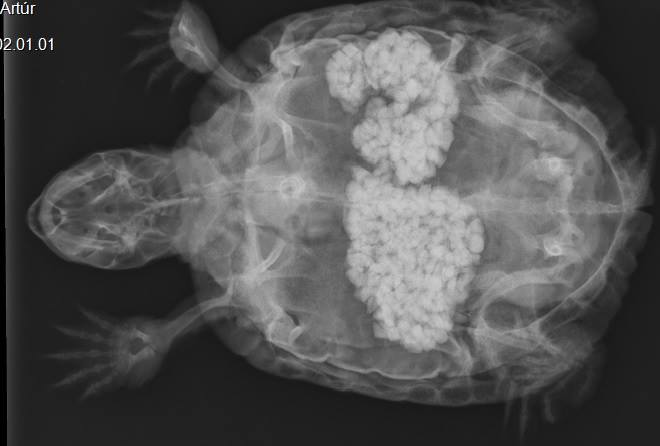

Már 2 hete nem evett, de egyébként élénk volt. A fizikális vizsgálat során kiderült, hogy valami oda nem illő kemény dolog van a hasüregében. A röntgenfelvétel megmutatta, hogy nagy mennyiségű kavics gyűlt össze a bélcsatornában. Először gyógyszeres kezeléssel próbálkoztunk, de az nem hozott eredményt, a kavicsok a kontroll röntgenen semmilyen elmozdulást nem mutattak. Ekkor döntöttünk a műtét mellett.